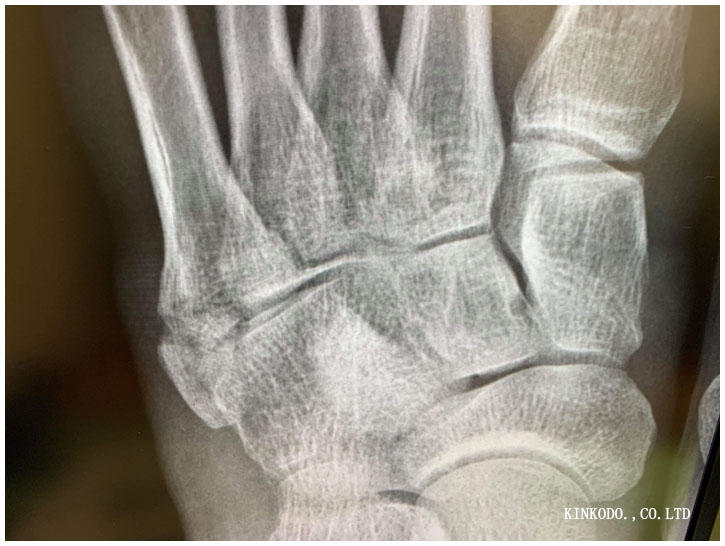

これ2週間前。

そして今日。

この丸の部分。素人が見てもくっついているよね。と思ったら。

確かにモヤモヤとはしているけど、まだ仮骨はできていないようで、この後エコーで見て貰ってもまだ見えないとのこと。